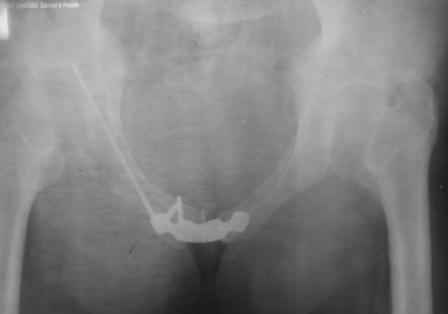

Уважаемые коллеги! Мы хотели узнать Ваши мнения или есть у кого либо опыт по закрытому остеосинтезу лонной кости винтом. Дело в том, что нами недавно впервые в нашей клинике проведен закрытый остеосинтез лонной кости канюлированным винтом. Пациент поступил с д-зом: Политравма(PTS-42 балла). закрытый 6-В2 перелом таза. тупая травма живота. Разрыв селезенки. ЗЧМТ.УГМ.При поступлении шинирование таза передней рамой, в противошоковом зале проведен КТ, где выявлен перелом лонной и седалищной кости со смещ. КПС целый, боковая масса крестца без смещения (компрессионный), damage control, спленэктомия. На 5 сутки с момента поступления проведена вышеописанная операция, длительность операции 25 мин, разрез 3 мм под шляпку винта, на ЭОП-е и x-ray "вход и выход таза" винт расположен в лонной кости внутрикостно. Теперь сам вопрос: когда вертикализировать, есть ли у кого нибудь наблюдения по осложнениям (пациент на 2 сутки послеоперации встал и пошел без никаих проблем (наркоз СМА, подутро прижало по мальенкому). Помню, где-то видел подобные снимки, никак не могу найти (по моему у А.Ф. Лазарева). К сожалению, по техническим причинам никак не могу загрузить фото, уже 2 час пытаюсь не получается. Скрывать не буду, операция предоставило огромное удовольствие, технически не трудно выполнить, чем пластину ставить. Даже появилась идея предложить блокированный штифт для лона. Ерсин Жунусов.

в архиве нашел подобный случай

С Уважением А.Миронов(Новокузнецк)

Уважаемый коллега! Огромное спасибо за рекомендации и иллюстрации! Задний комплекс, а точнее КПС не стал фиксировать т.к. само сочленение и суставная поверхность крестца целое, на кт-срезе имеет место краевой перелом и то не завершенный, учитывая что передняя связка КПС целая (а она сами знаете мошная)не стали фиксировать и клинический пациент не регировал, только КТ. Еще на Ваших фото винты вошли через кортикальный слой или ближе к перелому, а у нас вход в лон получилось прямо с мыса симфиза, т.е. перелом слева, винт зашел справа налево. Или это не принципиально?. С уважением Ерсин Жунусов.